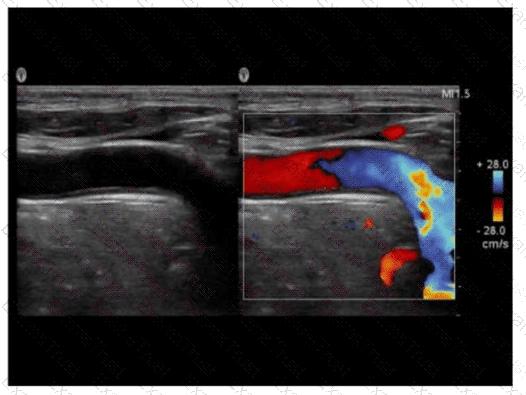

Which pulsed-wave Doppler adjustment would be appropriate to correct the aliasing seen in this image?

Options:

A.

Increase the spectral Doppler gain.

B.

Decrease the spectral Doppler gain.

C.

Increase the Doppler pulse repetition frequency.

D.

Decrease the Doppler pulse repetition frequency.